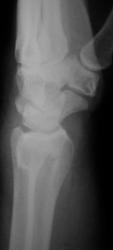

Пол пациента: Мужской пол Тип патологии: Травма Область исследования: Скелетно-мышечная система Методы исследования: Rg Травма. Пациент направлен врачом хирургом на рентгенографию лучезапястного сустава. Произведено исследование. Ваше мнение коллеги? Thu, 15/10/2009 - 21:47 #1 Наталия Offline Last seen: 8 years 8 months ago Joined: 30.07.2008 - 13:24 Posts: 538 Откол части шиловидного отростка локтевой кости, перелом лучевой кости в питичном месте, перелом ладьевидной кости. Может отрыв крючка. Thu, 15/10/2009 - 22:25 #2 v1tal Offline Last seen: 4 years 10 months ago Joined: 07.06.2008 - 19:41 Posts: 1779 Можно добавить краевой перелом кости-трапеции. "Знаешь, у некоторых врачей есть комплекс мессии — им необходимо спасать мир. А у тебя комплекс Рубика — тебе необходимо решать головоломки." Sun, 18/10/2009 - 23:33 #3 Катенёв Валенти... Offline Last seen: 7 years 1 month ago Joined: 22.03.2008 - 22:15 Posts: 54876 Так выходит - 3 перелома!? Mon, 19/10/2009 - 20:15 #4 Анатолий Владим... Offline Last seen: 7 years 11 months ago Joined: 16.10.2009 - 21:16 Posts: 1941 В ладьевидной кости в норме часто можно наблюдать ступеньку по наружному контуру, которая симулирует перелом. Для окончательного решения вопроса необходима рентгенограмма костей запястья в косой проекции.

Откол части шиловидного отростка локтевой кости, перелом лучевой кости в питичном месте, перелом ладьевидной кости. Может отрыв крючка.

Можно добавить краевой перелом кости-трапеции.

Так выходит - 3 перелома!?

В ладьевидной кости в норме часто можно наблюдать ступеньку по наружному контуру, которая симулирует перелом. Для окончательного решения вопроса необходима рентгенограмма костей запястья в косой проекции.